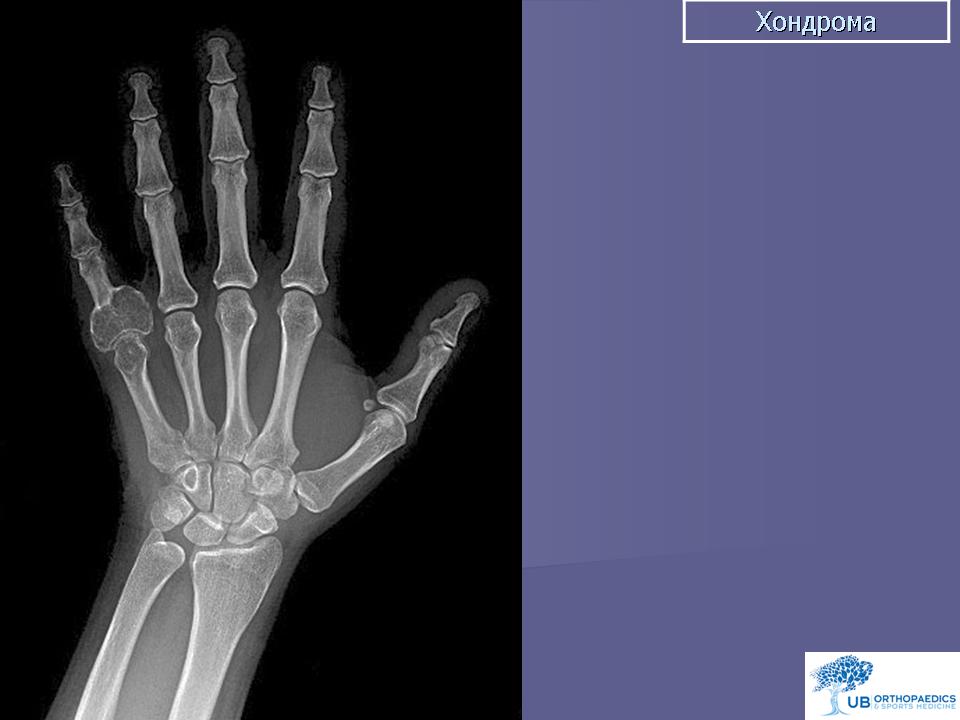

Хондрома. Встречается одинаково часто у лиц обоего пола, как правило, в возрасте 7-20 лет. Наиболее часто локализуется в костях кистей и стоп, но встречается также в костях таза, ребрах и длинных трубчатых костях. Хондромы составляют 10-15% от всех доброкачественных опухолей костей. Малигнизация хондром отмечается в 5% случаев. Хондромы могут быть одиночными и множественными. Если опухоль располагается внутри кости, ее называют энхондромой, на поверхности кости - экхондромой. В детском возрасте заболевание обычно протекает латентно. Клиническая картина бывает различной при энхондромах и экхондромах. Энхондромы характеризуются вначале при небольших размерах, бессимптомным течением, а затем в связи с ростом опухоли и давлением на корковый слой возникают боли. С течением времени боли усиливаются, появляется припухлость. При пальпации определяется плотная болезненная неподвижная по отношению к кости опухоль. Довольно частым осложнением бывает патологический перелом. При экхондроме ведущим начальным симптомом является наличие пальпируемой плотной опухоли, а также деформация пораженной части скелета. По достижении опухолью больших размеров наблюдаются симптомы нарушения функции близлежащих органов и тканей, особенно выраженные при опухолях костей таза. Диагностика хондром основывается на клинической картине и данных рентгенологического исследования. При экхондромах на рентгенограммах определяется участок уплотнения на фоне мягких тканей. Как правило, в этом участке видны очаги обызвествления, дающие крапчатый рисунок. В зависимости от степени обызвествления конфигурация опухоли на рентгенограммах выявляется более или менее четко. Основной рентгенологический симптом при энхондромах - изменения костной структуры. Степень их бывает различной в зависимости от выраженности процессов деструкции и обызвествления. Обычно в центре вздутого участка кости определяется одиночный очаг равномерного просветления, имеющий округлую или овальную форму и четкие контуры, резко отграниченный от неизмененной кости. На фоне просветления обнаруживаются крапчатые или хлопьевидные пятнистые тени, соответствующие очагам обызвествления хряща. В случаях, когда процессы деструкции слабо выражены, просветление может отсутствовать, кость представляется пятнисто разреженной, а в центральной части поражения видны конгломераты обызвествлений. Лечение хирургическое: при опухолях мелких костей и ребер - удаление пораженной кости, при хондромах костей таза - удаление опухоли с резекцией кости, при хондромах длинных трубчатых костей - резекция пораженного участка кости с одномоментным замещением дефекта трансплантатом. Важно тщательно соблюдать принцип абластики в ходе операции, поскольку клетки хондромы обладают большой способностью имплатироваться.

Хондрома. Хондромы, как указывает С. А. Рейнберг, наблюдаются преимущественно в детском и юношеском возрасте По данным Т. П. Виноградовой, возраст больных различен с преобладанием со второго по четвертое десятилетие жизни. Из 52 наблюдаемых нами больных хондромой большая половина была в возрасте 30—40 лет. Преобладание какого-либо пола среди больных не отмечается. В большинстве случаев поражаются короткие трубчатые кости кисти (примерно в 70% случаев), реже — стоп, затем кости таза, отростки позвонков, грудина. Длинные трубчатые кости поражаются весьма редко. В длинных трубчатых костях хондрома локализуется в метаэпифизарных концах. По данным И. Г. Лагуновой (1962), в среднем и пожилом возрасте хондрома в длинных трубчатых костях располагается в метафизе, распространяясь в эпифиз или диафиз. В наших наблюдениях превалировала метаэпифизарная локализация хондром. В детском возрасте хондромы в длинных трубчатых костях, как правило, поражают метафиз. В коротких трубчатых костях кисти и стопы хондромы чаще бывают множественными, причем отмечается двустороннее поражение. В плоских костях, и особенно в длинных трубчатых костях, наблюдаются солитарные хондромы. Суставы, как правило, не изменены. Но при больших размерах опухоли наступает выраженная деформация костей, механически препятствующих движениям в суставах.

Рентгенологическая картина энхондром довольно характерна. Определяются округлой и овальной формы очаги деструкции костной ткани. Эти очаги деструкции располагаются или центрально, вызывая вздутие кости, или эксцентрично. На хрящевом фоне могут выделяться одиночные костные перемычки и вкрапления извести. В ряде случаев эти известковые вкрапления бывают множественными, сливаются между собою и как бы заполняют весь хрящевой фон (очаг деструкции). Кортикальный слой неравномерно истончен, местами утолщен, не прерывается. В длинных трубчатых костях очаг деструкции, располагаясь в метаэпифизарном отделе, вызывает умеренное вздутие кости. Истонченный кортикальный слой, как правило, имеет ровные контуры. Возможна булавовидная деформация пораженного отдела кости. Вследствие поражения эпифизарных хрящей у детей может наблюдаться торможение роста кости в длину. Наблюдаются патологические переломы пораженной кости.